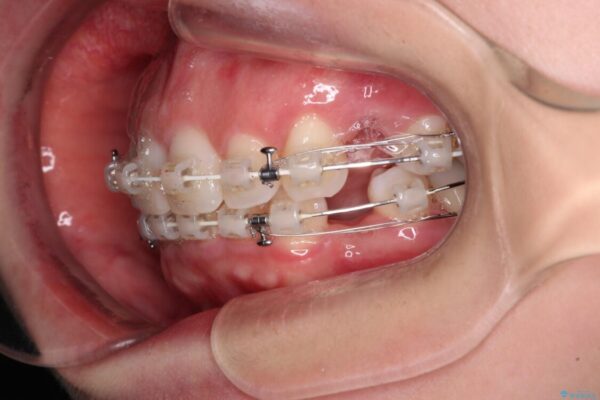

治療途中

• 【モニター】出っ歯と咬み合わせを改善 ワイヤー装置の抜歯矯正 治療途中画像

左下の大臼歯2本が顕著に舌側に傾斜しているため、まずは奥歯の咬み合わせを改善をし、その後上下左右の第1小臼歯4本を抜歯することで口元を引っ込めながら整えることとしました。